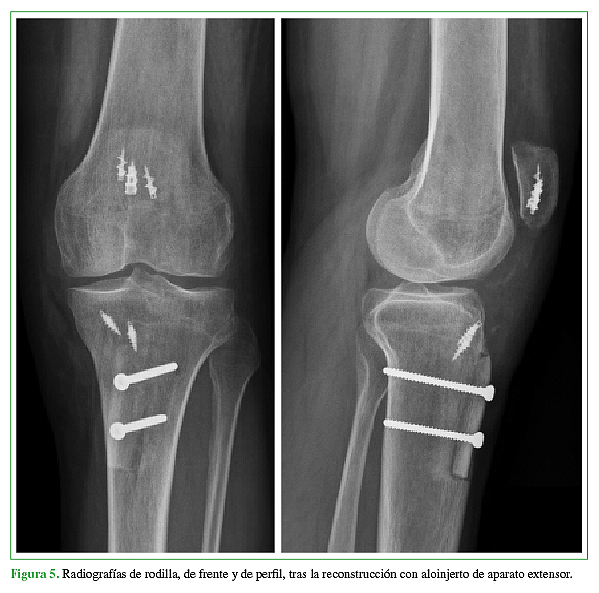

La rotura primaria del tendón rotuliano es una patología poco frecuente que afecta principalmente a adultos activos jóvenes. Aún menos frecuente, es la rotura crónica o recurrente del tendón rotuliano, y es esta última situación, la que presenta una importante dificultad técnica a la hora de realizar el debido tratamiento quirúrgico. El objetivo de este trabajo es la presentación de un caso donde se realizó la reconstrucción quirúrgica del aparato extensor mediante la utilización de aloinjerto luego de haber presentado tres cirugías fallidas para la reparación del tendón rotuliano tras sufrir una lesión traumática del mismo. Se describe tanto la técnica quirúrgica como también el protocolo de rehabilitación.Descargas